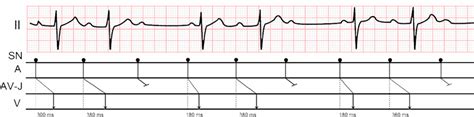

Let’s dig a little deeper into why these Wenckebach AV block symptoms occur, shall we? At its core, Wenckebach, also known as Mobitz type I second-degree AV block, is all about a progressive delay in the electrical impulse as it travels through the AV node. Imagine the AV node as a crucial junction box in your heart’s wiring. Normally, it delays the signal just enough to let the atria contract fully before the ventricles do. In Wenckebach, this delay gets longer and longer with each beat until, eventually, one signal completely fails to get through, resulting in a dropped beat (a P wave without a QRS complex on an EKG). After that dropped beat, the cycle usually resets, and the conduction normalizes for a bit before the progressive delay starts again. This pattern of progressively lengthening PR interval followed by a dropped QRS complex is the hallmark of Wenckebach. Now, how does this electrical glitch translate into symptoms like fatigue and dizziness? When beats are dropped, your heart rate temporarily slows down. This reduced heart rate means your heart is pumping less blood with each minute. This decreased cardiac output can lead to insufficient blood flow to the rest of your body, particularly to vital organs like the brain and muscles. That’s why you feel dizzy – your brain isn’t getting enough oxygenated blood. That’s also why you feel fatigued – your muscles aren’t getting the fuel they need. If the dropped beats are frequent or if the underlying heart rate is already slow, these symptoms can become quite pronounced. In some cases, especially if the Wenckebach block is occurring in conjunction with other heart conditions or if the heart rate drops very low, it can even lead to fainting. The key takeaway here is that the symptoms are a direct consequence of the heart’s inability to maintain an adequate heart rate and cardiac output due to the intermittent failure of electrical signal conduction through the AV node. Understanding this mechanism is the first step in appreciating the significance of the symptoms.

Now, let’s talk about diagnosing Wenckebach AV block symptoms . If you’re experiencing any of the signs we’ve discussed – persistent fatigue, dizziness, shortness of breath, or even fainting spells – the first thing you need to do is schedule an appointment with your doctor . Seriously, don’t brush these off! Your doctor will likely start by taking a detailed medical history, asking about your symptoms, when they occur, and any other health conditions you might have. They’ll also perform a physical examination, which will include listening to your heart with a stethoscope to check for any irregular rhythms or skipped beats. But the real star of the show when it comes to diagnosing Wenckebach is the electrocardiogram (EKG or ECG) . This is a non-invasive test that records the electrical activity of your heart. On an EKG, Wenckebach typically shows a characteristic pattern: the PR interval (the time it takes for the electrical signal to travel from the atria to the ventricles) gets progressively longer with each beat, until eventually, a QRS complex (representing ventricular contraction) is dropped. This pattern is called a